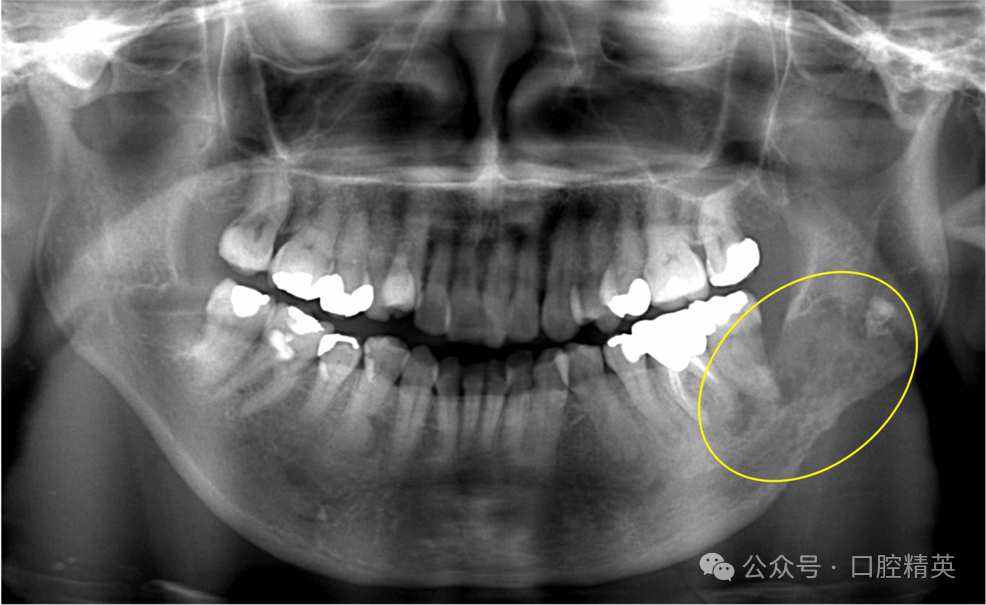

进一步CT检查显示,36、37及38周围舌侧骨皮质存在不规则吸收(图2)。

图2 初诊CT影像

36-38区域轴位(A)、冠状位(B)、矢状位(C)影像可见舌侧骨皮质不规则吸收(黄圈示骨皮质破坏关键表现)。